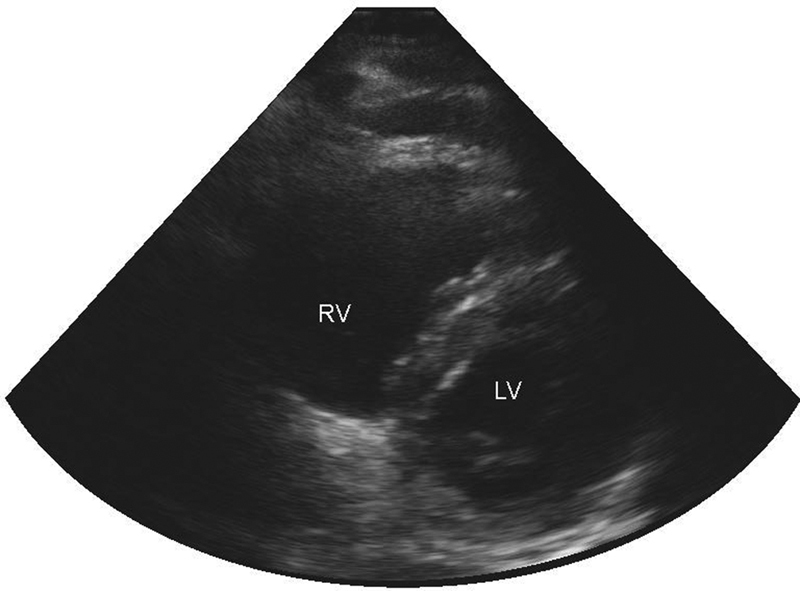

在大面积肺栓塞(PE)患者中,抗凝和溶栓药物可能会增加为体外血液动力学支持而进行血管插管后腹膜后出血的风险,从而导致腹腔隔室综合征(ACS)。一名妊娠 33 周的 27 岁女性出现急性胸痛和气短。诊断为大面积肺栓塞。开始静脉注射非分 子肝素,同时输注导管引导的组织纤溶酶原激活剂(tPA)和机械血栓切除术。在手术过程中,心脏骤停。医生进行了心肺复苏、静脉注射 tPA 和紧急围产期剖宫产。恢复自主循环后,右心室严重衰竭,需要静脉动脉膜供氧。六小时后,腹膜后出血继发 ACS,需要手术干预。体外血流动力学支持插管后腹膜后出血可能导致 ACS。

In massive pulmonary embolism (PE), anticoagulation and thrombolytics may increase the risk of retroperitoneal bleeding following vascular cannulation for extracorporeal hemodynamic support resulting in abdominal compartment syndrome (ACS). A 27-year-old women at 33 weeks of gestation presented with acute chest pain and shortness of breath. Massive PE was diagnosed. Intravenous unfractionated heparin was started together with catheter-directed tissue plasminogen activator (tPA) infusion and mechanical thrombectomy. During the procedure, cardiac arrest developed. Cardiopulmonary resuscitation, intravenous tPA, and urgent perimortem cesarean delivery were performed. After return of spontaneous circulation, profound right ventricular failure required venoarterial membrane oxygenation. Six hours afterward, ACS secondary to retroperitoneal bleeding developed, requiring surgical intervention. ACS may result from retroperitoneal bleeding following cannulation for extracorporeal hemodynamic support.